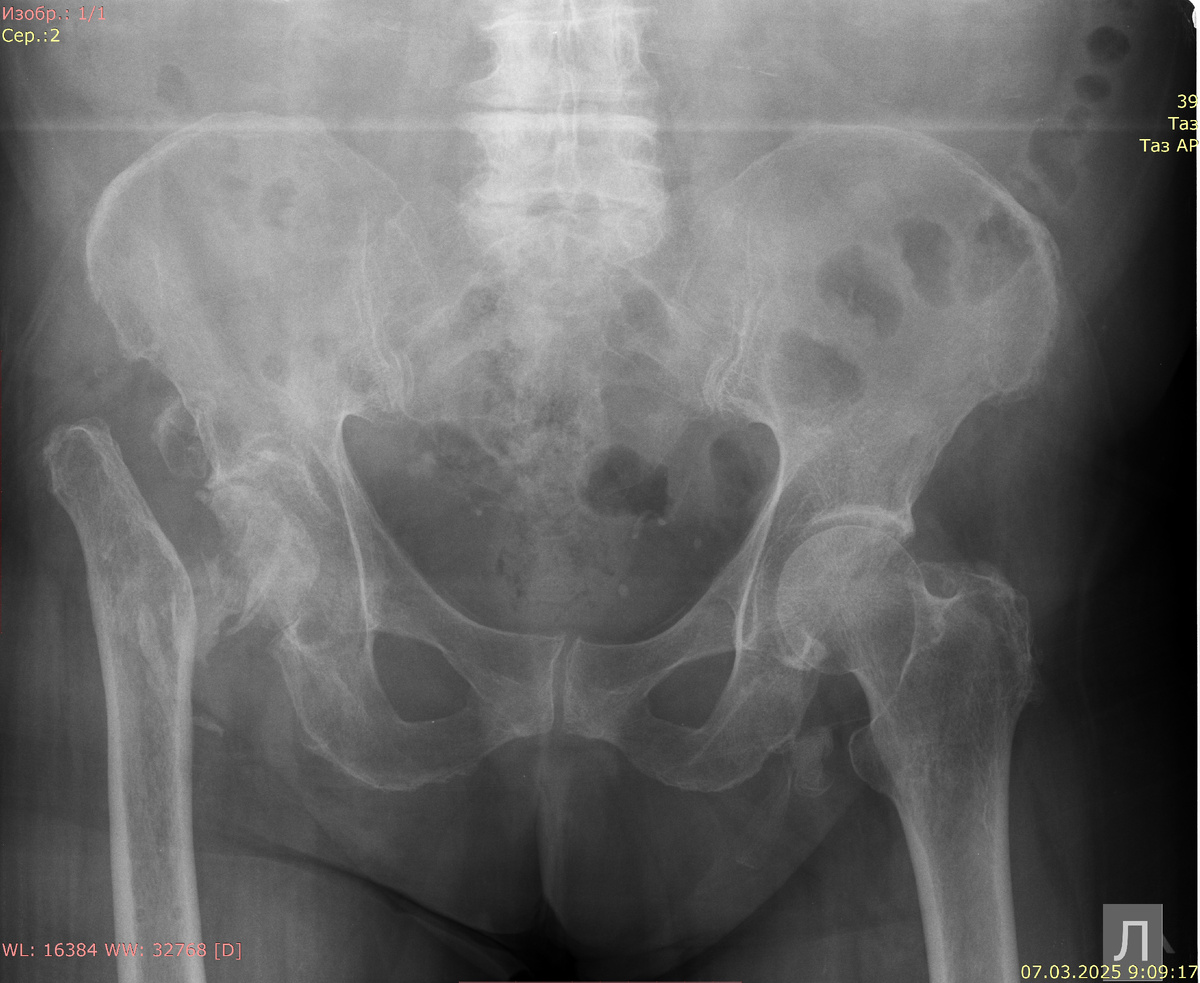

Рентгенография обоих тазобедренных суставов в прямой проекции:

Вертужная впадина четко не определяется, остеопоретична. В ней полуокружность головки бедренной кости: деформирована и склерозирована. Шейка бедренной кости отсутствует. На месте шейки оссифицированные мягкие ткани. Диафиз бедренной кости расположен выше левой на 5 см. ЛЕВЫЙ ТАЗОБЕДРЕННЫЙ СУСТАВ

Суставные поверхности тазобедренного сустава конгруэнтны, головка бедренной кости центрирована в суставной впадине. Головка бедренной кости обычной формы и структуры. Шейка бедренной кости не укорочена, шеечно-диафизарный угол в пределах нормальных показателей. Вертлужная впадина обычной формы и структуры, склерозирована. Суставная щель в тазобедренном суставе сужена с минимальным значением до 2 мм. Суставные поверхности уплотнены, в субхондральном слое остеосклероз. Параартикулярные ткани без патологических рентгенопозитивных включений. Костно-деструктивных и костно-травматических изменений не выявлено.

Заключение: неконсолидированный перелом правого бедра, краниальное смещение правой бедренной кости. Коксартроз слева 2 степени